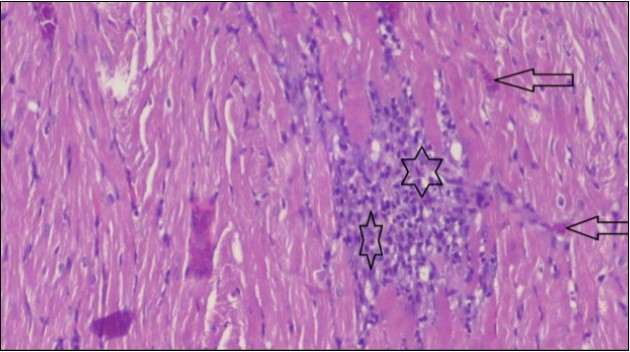

An important organ that is affected directly by the obesity which is the heart: The heart is the main important organ in circulatory system, the heart wall has three basic layers; the tunica intima of the heart is called endocardium, the tunica media of the heart is called the myocardium, the tunica adventitia of the heart the epicardium. The histological examination of the hearts of control rats feeding standard diet showing normal cardiac tissue with elongated, unbranched multinucleated muscle fibers (arrow), (Figure 1). The rats are feeding (HFD) for 2 weeks (obese rats) showing large number of inflammatory cells (star), degeneration muscles fiber ,circle and congested Blood vessels (arrow) (Figure 2). By comparison hearts of rats are treated by fennel after obesity and control rats observed show improved cardiac tissue with less infiltration (star) and well organized elongated muscle fibers with peripheral nuclei (arrow) (Figure 3). While examination of rats heart that treated by ator after obesity appears show less improved cardiac tissue with few inflammatory cells between disorganized muscle fiber (star), (Figure 4). While combined hearts of rats are treated by fennel and ator after obesity and control mice are showing nearly cardiac tissue with well-organized muscles fibers (arrow), (Figure 5).

Figure 2.Photomicrograph of heart section of an obese rat showing large number of inflammatory cells (star), degeneration muscles fiber, circle and congested Blood vessels (arrow), (H&E) (400X).

Figure 3.Photomicrograph of heart section of treated rat with fennel herb showing improved cardiac tissue with less infiltration (star) and well organized elongated muscle fibers with peripheral nuclei (arrow), (H&E) (400X).

Figure 4.Photomicrograph of heart section of treated rat with Ator drug showing less improved cardiac tissue with few inflammatory cells between disorganized muscle fiber (star), (H&E) (400X).

These results were confirmed with histological changes of feeding rats heart tissues with high fat diet only, which showed vaculation of tunica media and narrowing in the lumen of aorta sections as well as congestion of cardiac blood vessel and hyalinosis of its wall. This result was confirmed by Szilvassy et al., 78, who indicated that although hyperlipidemia increases oxidative stress in the cardiovascular system, it renders the heart and the vasculature more susceptible to stress. Ouwens et al. 79 identified that development of hyper-cholestremia, which is one of the risk factors for cardio vascular diseases is associated with increased blood levels of TC, LDL-C and VLDL-C as well as lowered levels of HDL in rats fed on high fat-diet. This result was confirmed by histological study, which revealed apparent normal histological structure of heart in all treated rats with fennel seeds. Epidemiologic studies have shown an inverse correlation between HDL-C level and the risk of cardiovascular disease. Increasing the HDL cholesterol level by 1mg may reduce the risk of cardiovascular disease by 2 to 3 percent 80. The present data agreed with Fatiha et al. 81, who reported that hyper-lipidemic rats treated with fennel extract had significant decrease in plasma levels of TL, TG, TC, LDL-C and VLDL, and significant increase in HDL-C level. The current study demonstrates that the alteration induced by high fat diet causing changes in blood parameters. These changes are exhibited through a decrease in RBCs, Ht, Hb and platelet and these changes could be due to oxidative stress, which lead to lipid peroxidation in RBCs membranes, auto oxidation of hemoglobin. As regards the total WBCs, lymphocytes and monocytes showed a marked decrease. While a distinct increase in the percentage of neutrophils and esinophils. The present, demonstrates that rats treated with (fennel), (ator) and (fennel with ator) exposure provided significant protection to the altered haematological variables. The effect of the treatment with fennel and ator is more effective than fennel only or ator only. The current study showed that the serum levels of the total protein and albumin in the obese group were significantly higher than those of the control group. The administration of (fennel) revealed significant decrease in the serum levels of the albumin and total protein as compared to the obesity group, although the serum levels of the albumin and total protein of the Ator group less than the obesity group. Otherwise, the levels of the total protein and albumin in fennel and Ator group were near to the similar value of the control group. The finding of this study indicates that the concentration of Malondialdehyde (MDA) and Myeloperoxidase (MPO) in liver homogenates of the fennel and ator group significant decrease than group (3) and group (4) and obesity group. There is a growing awareness that obesity is a prime risk factor for the development of dyslipidemia profile and that oxidative stress may play a role in various adverse effects of obesity.